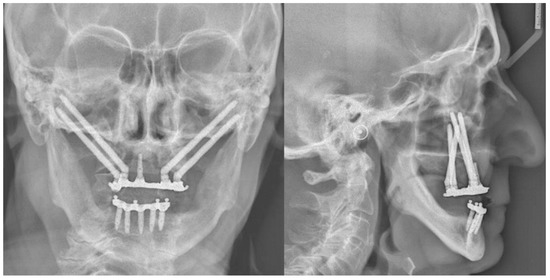

2. Case Report

- Step 4. Surgery: navigation of the drill along the predefined surgical plan.